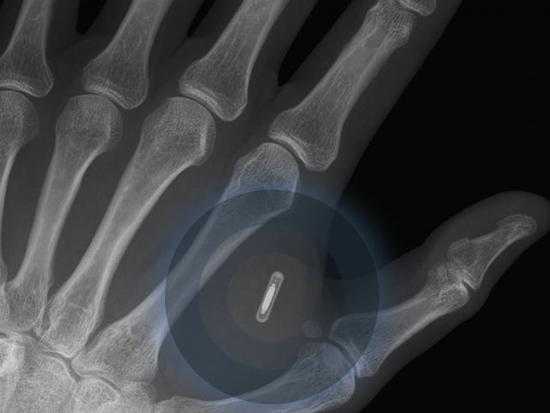

6.2025年,首款植入式手机将商业化

2023年,依附于手机将会是一个全新的概念。报告称,约80%的受访者认为在七年内,第一部植入式手机将会商业应用。该设备能更准确追踪个人健康状况,也能通过脑电波或信号来与人进行思想交流。植入式医疗设备,例如心脏起搏器和植入式耳蜗等已成为主流。2025年内之前我们将会看到更多植入式设备的广泛应用。